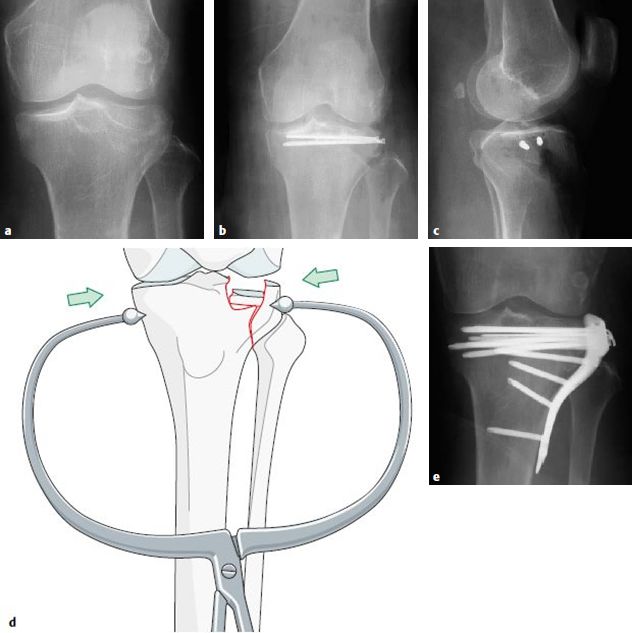

图6.8.1-16 a-e 排钉技术可以用来维持复位后的关节面

a 关节面塌陷;b-c 两枚2.7mm锁定螺钉维持复位后关节面;d 使用大的骨盆复位钳来复位胫骨平台劈裂骨折;e 额外的外侧锁定钢板提供排钉支撑

关节面的压缩得到复位后,必须考虑如何维持:简单的劈裂型关节骨块可以通过拉力螺钉固定,但是塌陷型骨折需要在抬高后的关节面软骨下采用2.7或3.5mm的皮质骨螺钉予以排钉固定(图6.8.1‑16a‑c)。对于严重的关节面分离移位,可采用colinear复位钳或骨盆复位钳来夹持复位已经增宽的胫骨平台(图6.8.1‑16d)。

股骨牵开器或外固定架可以帮助间接复位。若胫骨平台骨折累及胫骨干,术中需要牵引利用软组织整复术以纠正短缩、旋转和成角畸形。借助锁定加压钢板的结合孔,打入皮质螺钉有助于骨折复位的最终调整;也可以发挥钢板的支撑功能来作为骨折复位的工具(图6.8.1‑16e)。